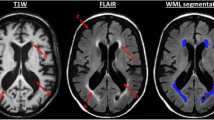

However, as the presence of mild to moderate WM hyperintensities (WMHs) commonly accompanies ageing and neurodegenerative diseases [22], we graded the WMHs using the Fazekas scale [23] on the basis of visual assessment in both periventricular (0 = absent, 1 = caps or pencil lining, 2 = smooth halo, 3 = irregular periventricular hyperintensities extending into the deep WM) and subcortical areas (0 = absent, 1 = punctate foci, 2 = foci beginning to become confluent, 3 = large confluent areas). The total Fazekas score was calculated by adding the periventricular and subcortical scores together [24] and was regressed out in the following statistical models. Detailed information can be found in Table 1.

The increases in MD, AD, and RD in mild COPD patients relative to the comparison group were not statistically significant. Moderate COPD patients showed increases in MD and AD in the splenium of the corpus callosum, left posterior corona radiata and external capsule relative to the comparison group. Additional increases in MD were detected in the right superior corona radiata, genu and body of the corpus callosum; the left posterior thalamic radiation; and the bilateral cingulum (cingulate gyrus). RD was observed in the left longitudinal fasciculus (Fig. 2).

TBSS results showing the differences in diffusion indices between moderate COPD patients and the comparison group Note: Green represents the mean WM skeleton of all subjects; yellow, red and blue represent regions with increased MD, increased AD and increased RD, respectively, in moderate COPD patients (P < 0.05, FWE corrected). Abbreviations: TBSS, tract-based spatial statistics; COPD, chronic obstructive pulmonary disease; NCs, normal controls; WM, white matter; MD, mean diffusivity; AD, axial diffusivity; and RD, radial diffusivity